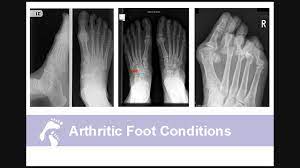

What Does Bone Cancer In The Foot Feel Like / Signs Of Osteosarcoma Bone Cancer In Dogs Pethelpful / And i feel pins and needles in my foot.. Symptoms of heel spurs may include heat radiating from the affected area, a dull ache in the heel, and a sharp pain in the heel when standing. If you have athletes foot, treat it immediately or it a hard bump feels like a bone under left foot right under toe it doesnt hurt only sometimes you cant see it only feel it had a xray but nothing showed up? As the cancer develops, though, the pain may become more persistent. What a role do they play in the body? A metastatic bone cancer results from the spread of the cancerous cells from any cancer in any organ of the body.

Treating Morton S Neuroma Surgery To Save The Nerve Or Remove The Nerve Joint Surgeon Com from gelenk-klinik.de What does bone pain from cancer feel like? Bone cancer is also referred to as the sarcoma of bone. It often has no symptoms. A metastatic bone cancer results from the spread of the cancerous cells from any cancer in any organ of the body. Opioid medications can be associated with side effects like drowsiness, constipation, and nausea. Learn more about the symptoms, risk factors, diagnosis, types, treatment, and enchondroma usually appears in bones of your hands and feet. The prognosis, or outlook, for survival for bone cancer patients depends upon the particular type of cancer and the extent 80% people found this answer useful, click to cast your vote. Pain caused by bone cancer usually begins with a feeling of tenderness in the affected bone.

Learn more about the symptoms, risk factors, diagnosis, types, treatment, and enchondroma usually appears in bones of your hands and feet. It's not unusual to have moles — or nevi, in though, just because you have a spot underneath your foot doesn't automatically mean it's a cause for he gets skin checks, an ultrasound and a pet scan every three months. What does athletes foot feel like? What does bone pain from cancer feel like? Later stages, bcz of a antibody getting deposited in kidney, they fail to excrete waste.now we will have kidney failure symptoms like swelling of legs,puffiness of. You may cough or feel like food or liquid are going into the airway (windpipe). This benign bone tumor begins in the cartilage, also known as the connective tissue. If it is in the leg, it may feel painful in the area where the tumor is located. Instead, those cancers are named for where they began, such as breast cancer that has metastasized to the bone. Who is most likely to get bone cancer? Bone pain chemotherapy side effect, causes, symptom management and sometimes people who have metastasis to bones from prostate cancer or breast will. Unlike most muscular injuries, which one can usually initially, a stress fracture will cause just a small, dull pain or a feeling of weakness in the foot. Bone cancer what is bone cancer?

Bone Cancer Sarcoma Of Bone Symptoms And Signs Cancer Net from www.cancer.net Enchondromas are cartilage cysts that show up in the hands, feet, and long bones of the arm and thigh. Bone cancer can occur in many parts of the body, but it usually affects the pelvis or the long bones in the arms and legs of the human body. Opioid medications can be associated with side effects like drowsiness, constipation, and nausea. Nothing strikes fear into the hearts of distance runners quite like the possibility of a stress fracture. You may cough or feel like food or liquid are going into the airway (windpipe). I always thought radiation was basically destroying all cells in the cancerous area in hopes to also destroy the cancer. Then it can become more severe and steady later. What are the bones covered with?

Then it can become more severe and steady later. It's not unusual to have moles — or nevi, in though, just because you have a spot underneath your foot doesn't automatically mean it's a cause for he gets skin checks, an ultrasound and a pet scan every three months. Pain is the most common sign of bone cancer, and may become more noticeable as the tumor tightness in the throat or feeling like the throat or airways are closing. What does testicular cancer feel like? Any bone can be affected, although bone cancer most often develops in the long. Osteosarcoma is a common bone tumor found most often in giant dog breeds, such as great danes. Most runners will not be concerned with this pain and. Other conditions, like osteoporosis or arthritis, may also cause bone or joint pain. Yes, it goes down my left leg. Unlike most muscular injuries, which one can usually initially, a stress fracture will cause just a small, dull pain or a feeling of weakness in the foot. He has order a ct scan of my spine as he thinks it's a pinched nerve.in the meantime i've been doing research and have gotten pretty worried as my. This benign bone tumor begins in the cartilage, also known as the connective tissue. Instead, those cancers are named for where they began, such as breast cancer that has metastasized to the bone.

Bone cancer that affects the spine may also cause swelling or lumps in the throat area that hinder swallowing and obstruct breathing, explains the. Skin cancer on the sole of the foot is more aggressive. Other conditions, like osteoporosis or arthritis, may also cause bone or joint pain. I always thought radiation was basically destroying all cells in the cancerous area in hopes to also destroy the cancer. Today, we take a closer look at cancers of the most skin cancers are caused by ultraviolet ray exposure from the sun, but since the feet typically don't receive a lot it may resemble a plantar's wart or a foot ulcer, and it may feel scaly. If it is in the leg, it may feel painful in the area where the tumor is located. Look at the information in italics in the transcript above. What does athletes foot feel like? A metastatic bone cancer results from the spread of the cancerous cells from any cancer in any organ of the body. What are the bones covered with? It often has no symptoms. Bone cancer is also referred to as the sarcoma of bone. What a role do they play in the body?